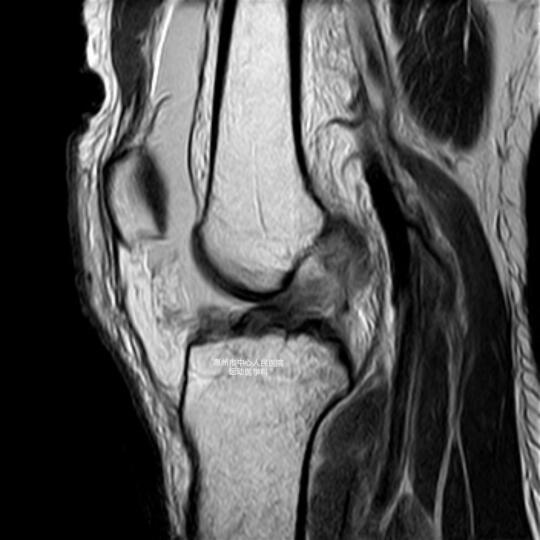

如果经验不足的非专科医生,这么处理或许就会漏诊了,这种胫骨平台外侧的骨折,又叫Segond骨折,提示合并了前交叉韧带损伤,这个片子是非常典型的Segond骨折,这个病人后续做了磁共振,结果是前交叉韧带完全断裂。

建议2周左右消肿后关节镜手术治疗,重建前交叉韧带。